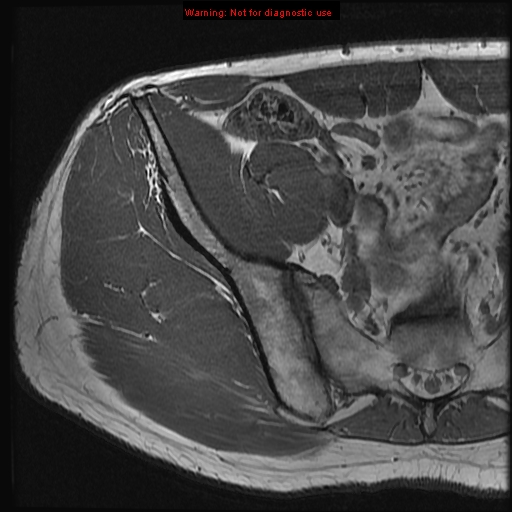

iliac crest

anterior superior iliac spine

piriformis muscle iliopsoas

iliopsoas

iliacus muscle

psoas muscle

rectus abdominus muscle

sartorius muscle

gluteus maximus muscle

lesser trochanter of femur

greater trochanter of femur

coccyx

multifidus muscle